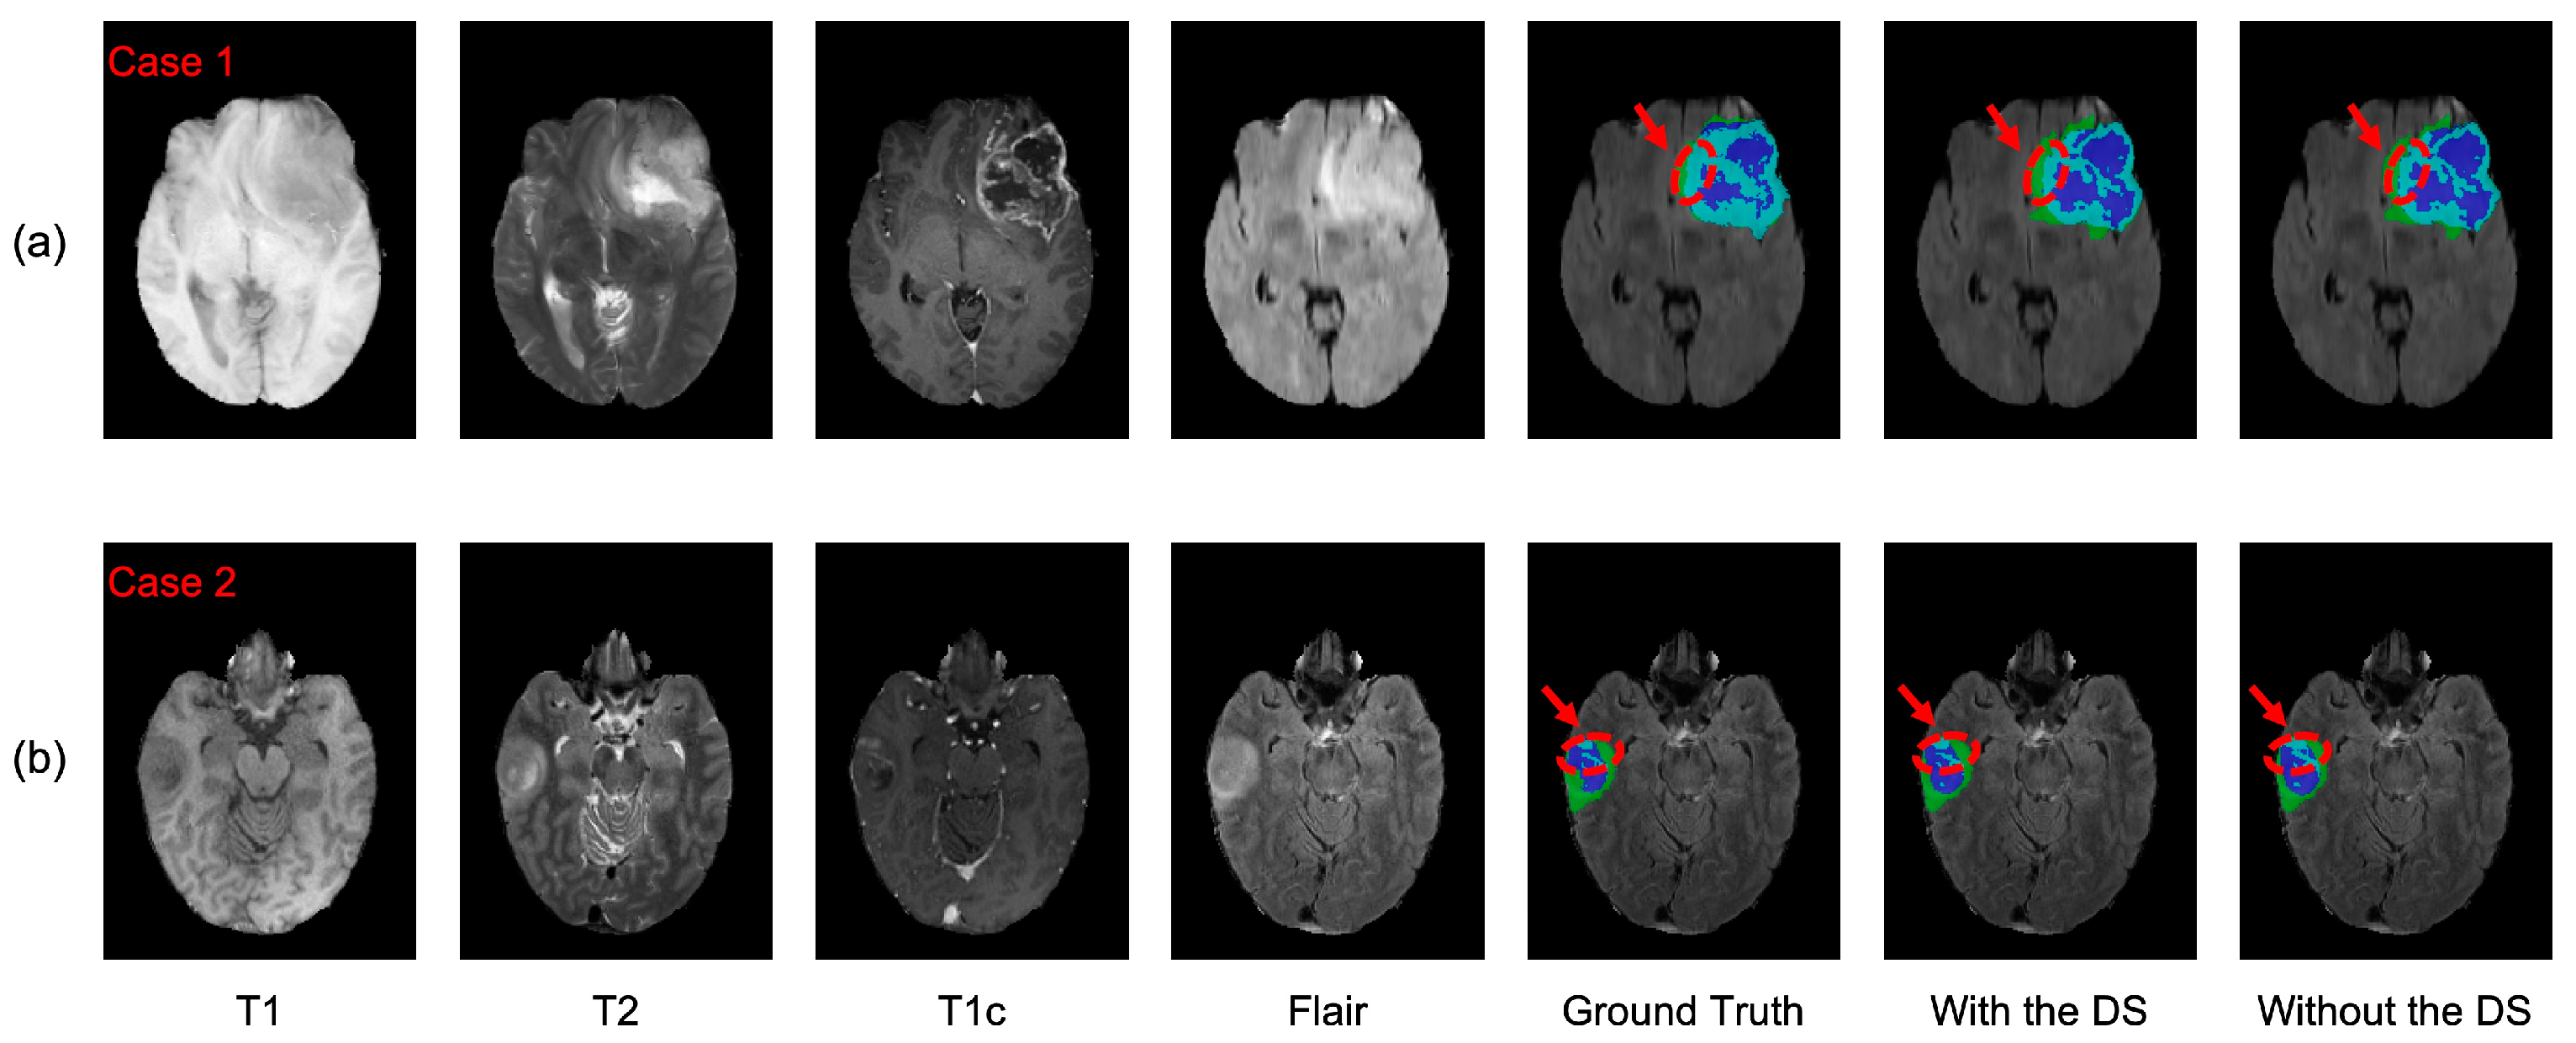

4.2.2. Analysis of the Deep Supervision Mechanism

4.2.3. Analysis of the Different Loss Functions